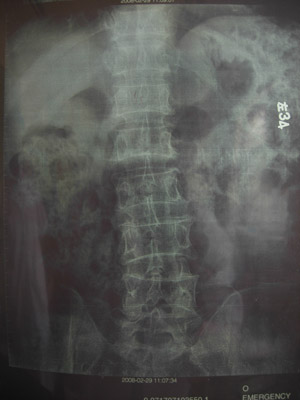

(本文附病历资料X线片)

病例一

术前X线片

病例二